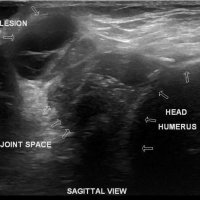

THE GEYSER SIGN IS A SUBCUTANEOUS PSEUDOTUMOR ABOVE THE ACROMIOCLAVICULAR JOINT

The geyser sign is a subcutaneous pseudotumor above the acromioclavicular joint, also known as AC joint cyst. The geyser sign is an infrequently encountered imaging sign that was originally described on conventional fluoroscopy-guided shoulder arthrography. The first case report of these cysts occuring in association with rotator cuff tears was made by Dr. Edward Craig in 1984, and again in 1986. The sign derives its name from its geyser-like appearance.

On physical examination, an AC joint cyst is a palpable fluid-filled mass. MRI scanning or a shoulder arthrogram should be obtained to evaluate the shoulder. Unenhanced MRI scans showing a large rotator cuff tear, a degenerated AC joint, and a large subcutaneous cyst adjacent to the AC joint is virtually patognomonic for the disease. Contrast administration on MR arthrogram will show the synovial fluid or intra-articular contrast extravasates from the glenohumeral joint into the subacromial bursa, into the AC joint, and then into an overlying cystic mass when a full-thickness rotator cuff tear is present, resembling a geyser spouting upwards.

Initial treatment is conservative and involves physical therapy along with aspiration. In patients with functional impairment or chronic shoulder pain who have failed conservative management, surgical treatment is recommended for both excision of the cyst and repair of the rotator cuff tear.